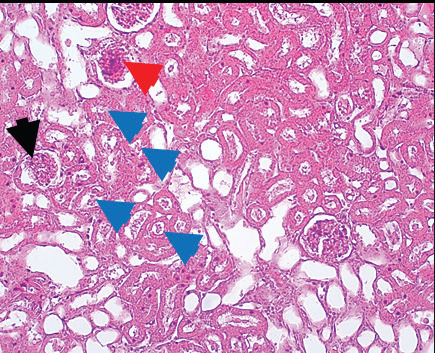

Results: The administration of gentamicin induced a decline in body weight and increases in the levels of inflammatory markers (kidney injury molecule I, tumor necrosis factor-alpha, and interleukin-6), urea, and creatinine, which are indicative of renal damage. Histopathological examination revealed extensive renal tissue damage. However, concurrent administration of gentamicin and GT diminished these parameters by decreasing the malondialdehyde concentration and improving the activity of antioxidant enzymes (glutathione peroxidase and superoxide dismutase). Furthermore, gentamicin injections caused nephrotoxicity, as evidenced by a reduction in body weight and higher levels of urea, creatinine, and inflammatory markers.